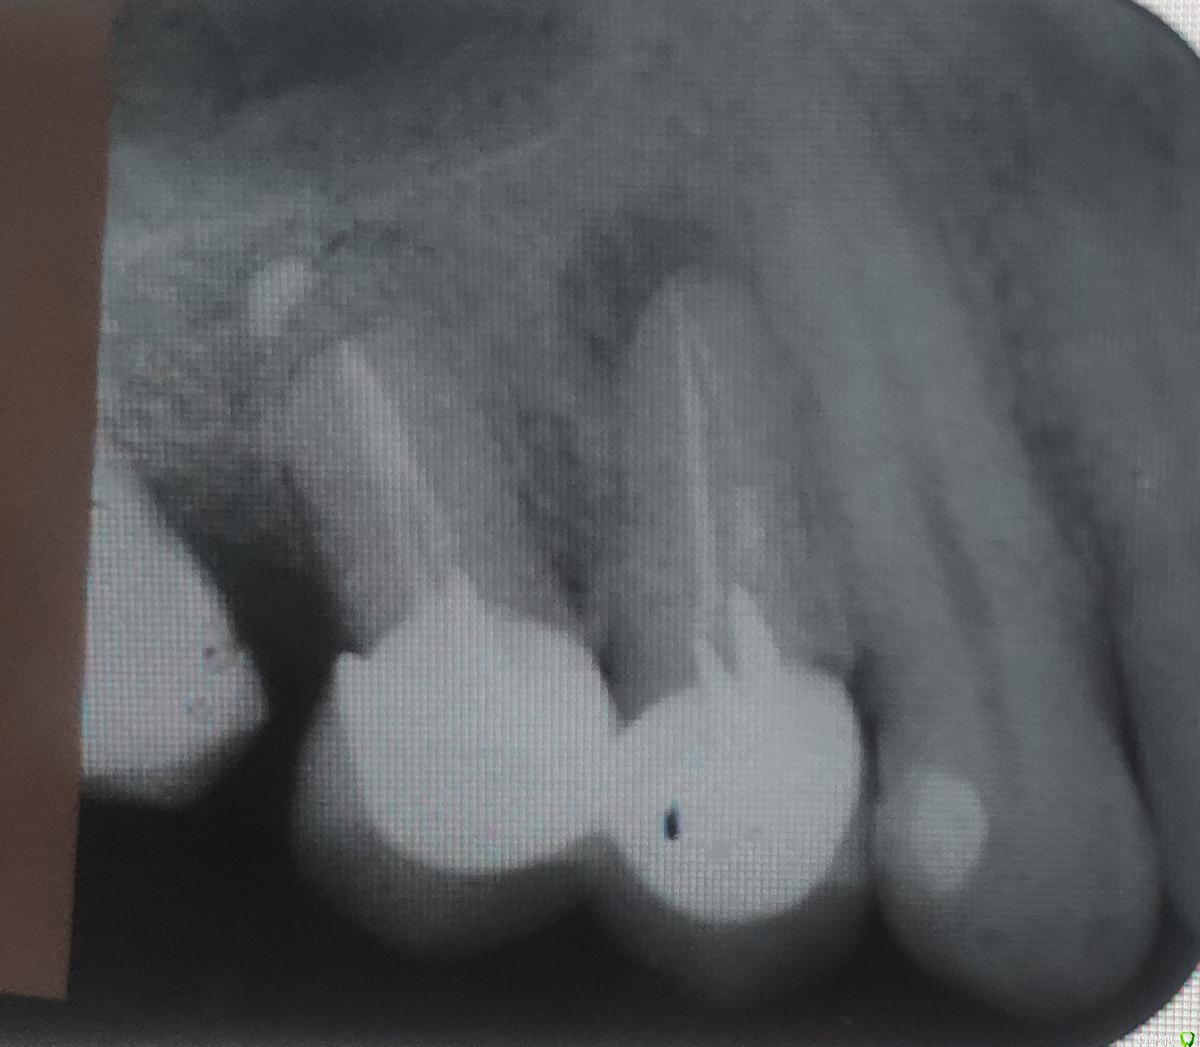

Александр9 Опубликовано 11 сентября, 2019 Автор Поделиться Опубликовано 11 сентября, 2019 Пока не дошел до врача. Успел только сделать рентген. Сам ничего разобрать на нем не могу. Насколько все серьезно? Надо ли обращаться к врачу который ставил мне эти коронки 3,5 года назад? Ссылка на комментарий

St. Опубликовано 11 сентября, 2019 Поделиться Опубликовано 11 сентября, 2019 Добрый день. Проблема в ближнем зубе под коронкой, там хроническое воспаление за пределами зуба, в период обострения оно "искало выход" и появился свищ. Нужно идти к стоматологу, поскольку само оно не пройдет, может только уменьшиться на время. Снять коронку, перелечить корневые каналы и после этого сделать новую коронку 1 Ссылка на комментарий